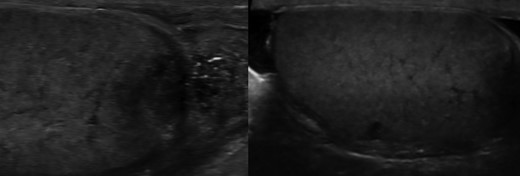

At a further check cystoscopy 1 month later, it was noted the patient continued to have right scrotal swelling and pain, as well as pus extruding from a sinus in the scrotal skin. Ultrasound scanning of the scrotum revealed a heterogenous focus of tissue calcification within the right epididymal tail, and inflammatory changes associated with granulomatous change (Fig. 1a and b).

a) and (b) Ultrasound scan showing heterogeneous focus of tissue calcification within the right epididymis and granulomatous change.

Various patterns of tuberculosis epididymitis and orchitis have been described, including diffuse hypoechoic heterogeneous enlargement, diffuse hypoechoic homogeneous enlargement, and nodular hypoechoic heterogeneous enlargement [6]. If present, as in our case, heterogenenic appearances are thought to result from the various stages of granuloma formation in response to mycobacterium infection [3]. Other features of tuberculous-epididymitis include hydrocele, cutaneous swelling, extratesticular intrascrotal calcifications, abscesses, and scrotal sinus tract [7].